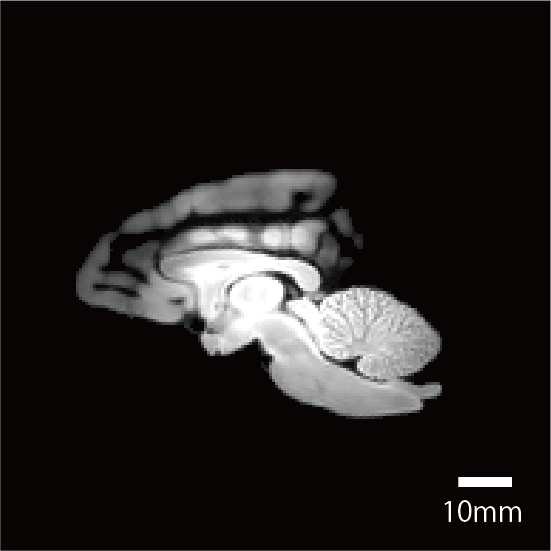

撮像情報

| T2強調画像 | 拡散テンソル画像 | |

| エコー時間 (TE) (秒) | 7.5 | 20 |

| 繰り返し時間 (RT) (秒) | 600 | 650 |

| 励起回数 (NEX) | 3 | 1 |

| 有効視野 (FOV) (mm) | 84, 67.2, 50.4 | 84, 67.2, 50.4 |

| マトリクスサイズ | 320, 256, 192 | 160, 128, 96 |

| 空間分解能 (µm) | 0.21 | 0.53 |

| b0 | - | 2 |

| 撮像時間 | 6時間 43分 | 53時間 14分 |

脳標本画像

| T2強調画像 |

![]() |